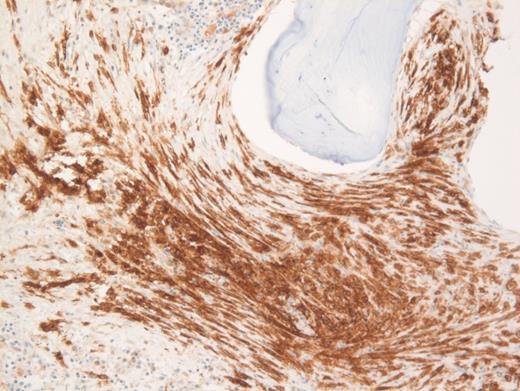

These results prompted a subsequent bone marrow biopsy. Peripheral blood smear showed rare abnormal circulating cells (Figure 1). Bone marrow core biopsy showed clusters of spindle cells adjacent to bony trabeculae (Figure 2) that were positive for CD117 (Figure 3). Scattered teardrop cells were also noted. Molecular testing by next-generation sequencing (NGS) detected diagnostic mutations.

Mast cell with metachromatic granules in circulation (Figure 1) with spindly clusters of compact mast cells in the biopsy (Figure 2) that are positive for CD117 (Figure 3) allows a diagnosis of systemic mastocytosis. These marrow spindly clusters of cells were also positive for mast cell tryptase and CD25. Mastocytosis is defined as multifocal infiltration by clonal proliferation of mast cells in one or more sites. They are broadly divided into cutaneous mastocytosis, systemic mastocytosis (SM), and mast cell sarcoma. The 2016 World Health Organization (WHO) classification of hematologic neoplasms separated them from myeloproliferative neoplasms. Cutaneous mastocytosis is restricted to the skin.

Neoplastic mast cells often assume a spindle shape on biopsy. All mast cells co-express CD117 and mast cell tryptase. However, when they express CD25, SM should be suspected. The mast cells in this case were positive for CD117, tryptase, and CD25 (not shown).